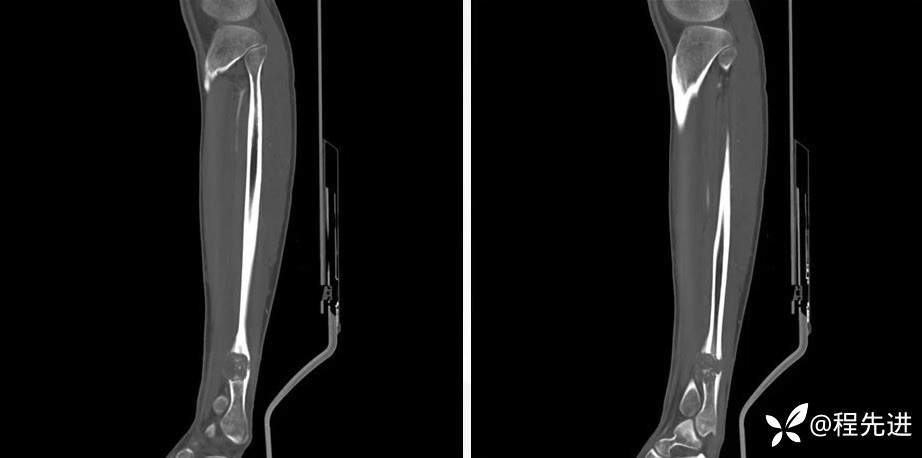

DR

CT平扫

CT骨窗